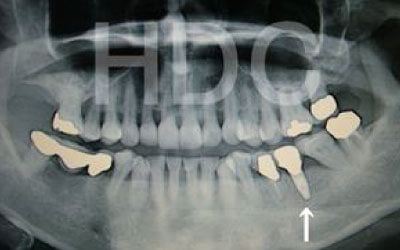

2 歯が傾いてくる、落ちてくる

歯は互いに支え合い、バランスを保っています。そのため、歯が抜けると支えがなくなり、抜けた部分の両隣の歯が傾いたり、上の歯が下に移動してきたりすることがあります。